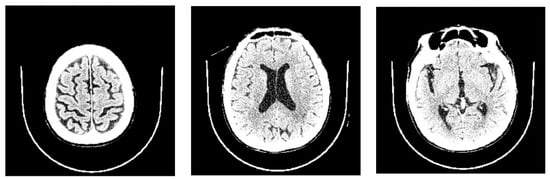

2.3. Radiologic Parameters

- Evans’ index: The ratio between the maximal width of the frontal horns of the lateral ventricles (B–C) by the maximal width of the inner table of the cranium in the same axial image [9].

- Narrow parietal sulci: At high-convexity and parafalcine region assessed in both axial planes in the most superior slices and coronal plane [10].

- Dilation of the Sylvian fissures: Reported as present or not present in the coronal plane compared with surrounding sulci [11].

- Focally enlarged sulci: Compared with surrounding sulci, usually found in coronal or axial planes [12].

- Temporal horns: Reported as mean width of the right and left side, measuring in the axial plane [11].

- Callosal angle: Angle between the lateral ventricles in the coronal plane through the posterior commissure perpendicular to the intercommissural plane [13].

- Periventricular hypodensities: Along the lateral ventricles graded as not present, present as a cap around frontal horns or confluently extending around the lateral ventricles [14].